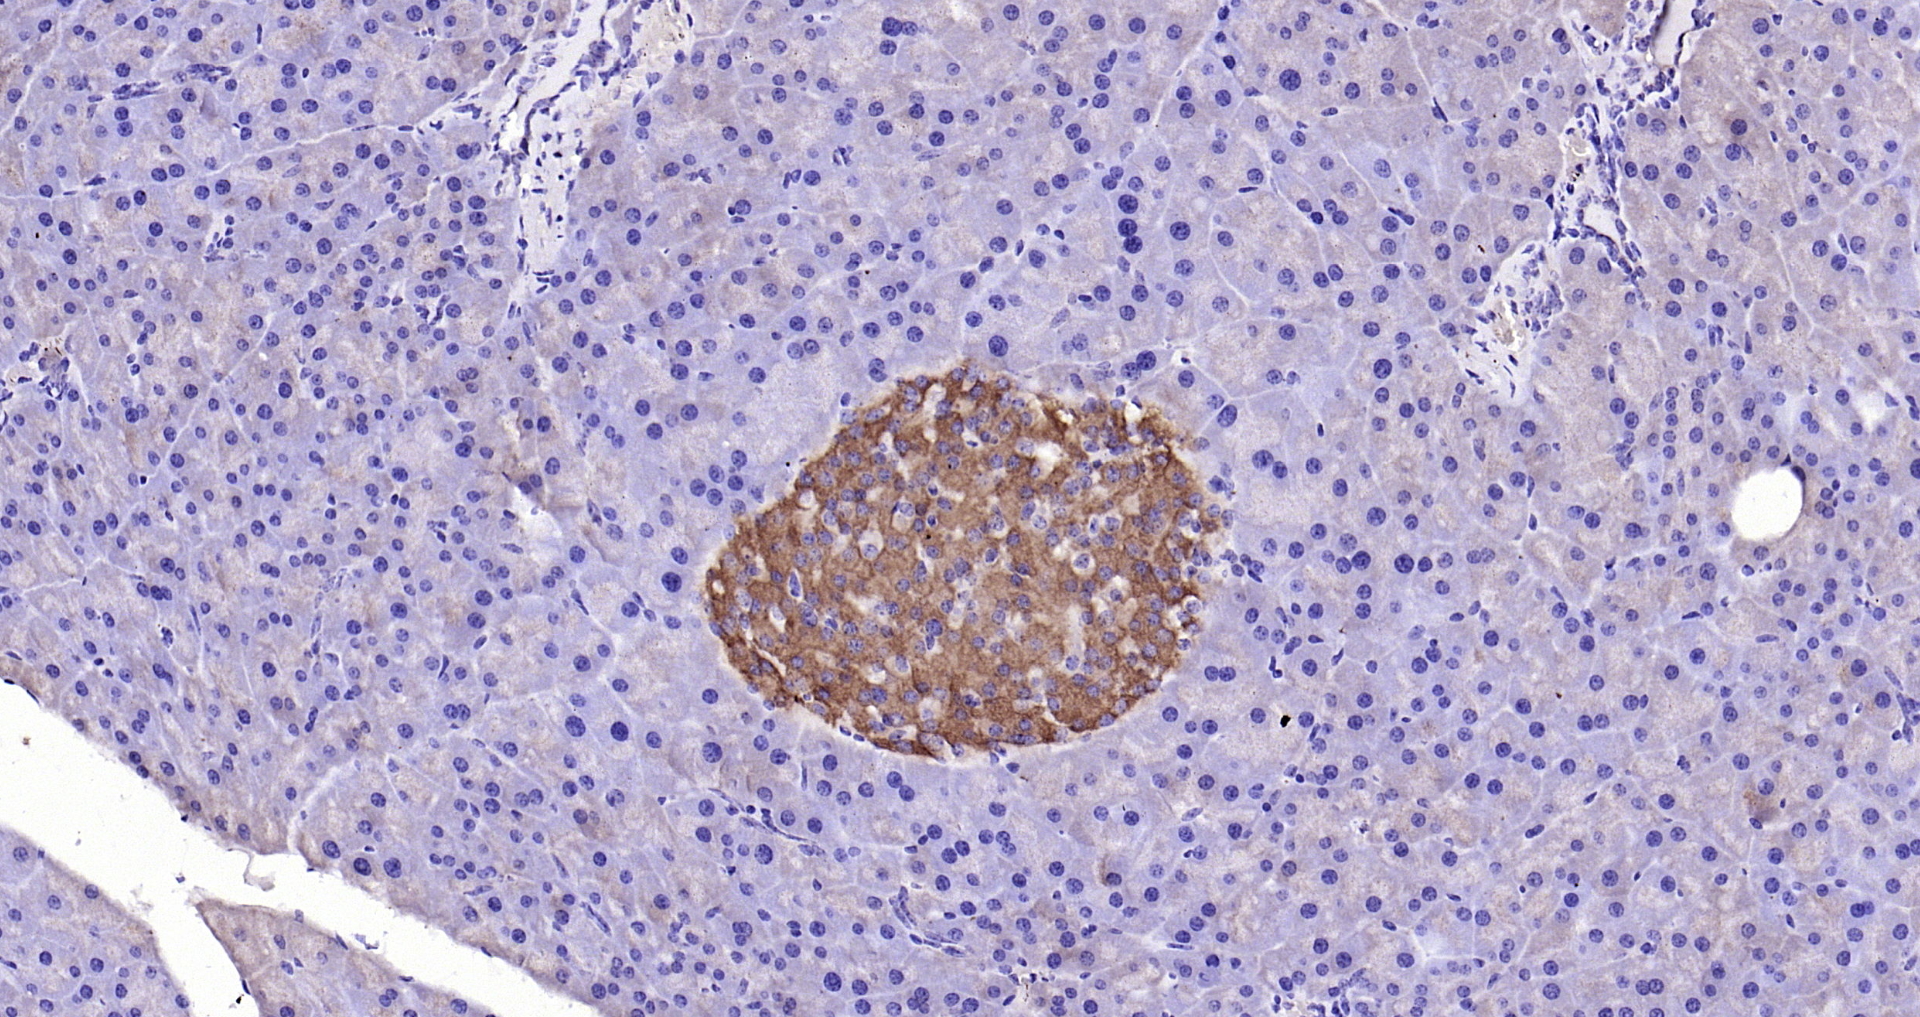

GPR49/LGR5 Polyclonal Antibody

• IHC-P

Catalog # bs-20746R

Product Name GPR49/LGR5 Polyclonal Antibody

IHC-P 1:200-400